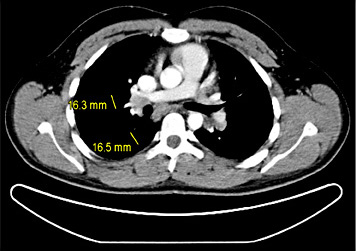

5th patient: this 23-year-old man underwent orchiectomy for marker-negative testicular seminoma at another institution. CT revealed intrathoracic nodules suspicious for mediastinal lymph node metastases. Accordingly, 4 cycles of BEP chemotherapy were administered. Restaging revealed unchanged mediastinal lymphadenopathy (Fig. 4). Then, the patient was referred to our institution for further management. Thorough pulmonological examination including transbronchial biopsy disclosed sarcoidosis-like lymphadenopathy, and thus metastatic disease was excluded. In view of these results, it must retrospectively be assumed that this patient had sarcoidosis synchronously with seminoma rather than having metastatic disease. Accordingly, the serum miR371a-3p level was RQ = 0.0 at the time of re-staging after chemotherapy. Unfortunately, no miR-levels were measured at the time of first presentation. Although speculative, one would assume that miR371a-3p levels had probably been low after orchiectomy for seminoma because the mediastinal lymphadenopathy had not changed ever since. By retrospective consideration, the normal marker level would have indicated the absence of metastases at the outset and accordingly, the patient could have been spared unwarranted chemotherapy and excessive diagnostic procedures apart from emotional distress from extended treatment.